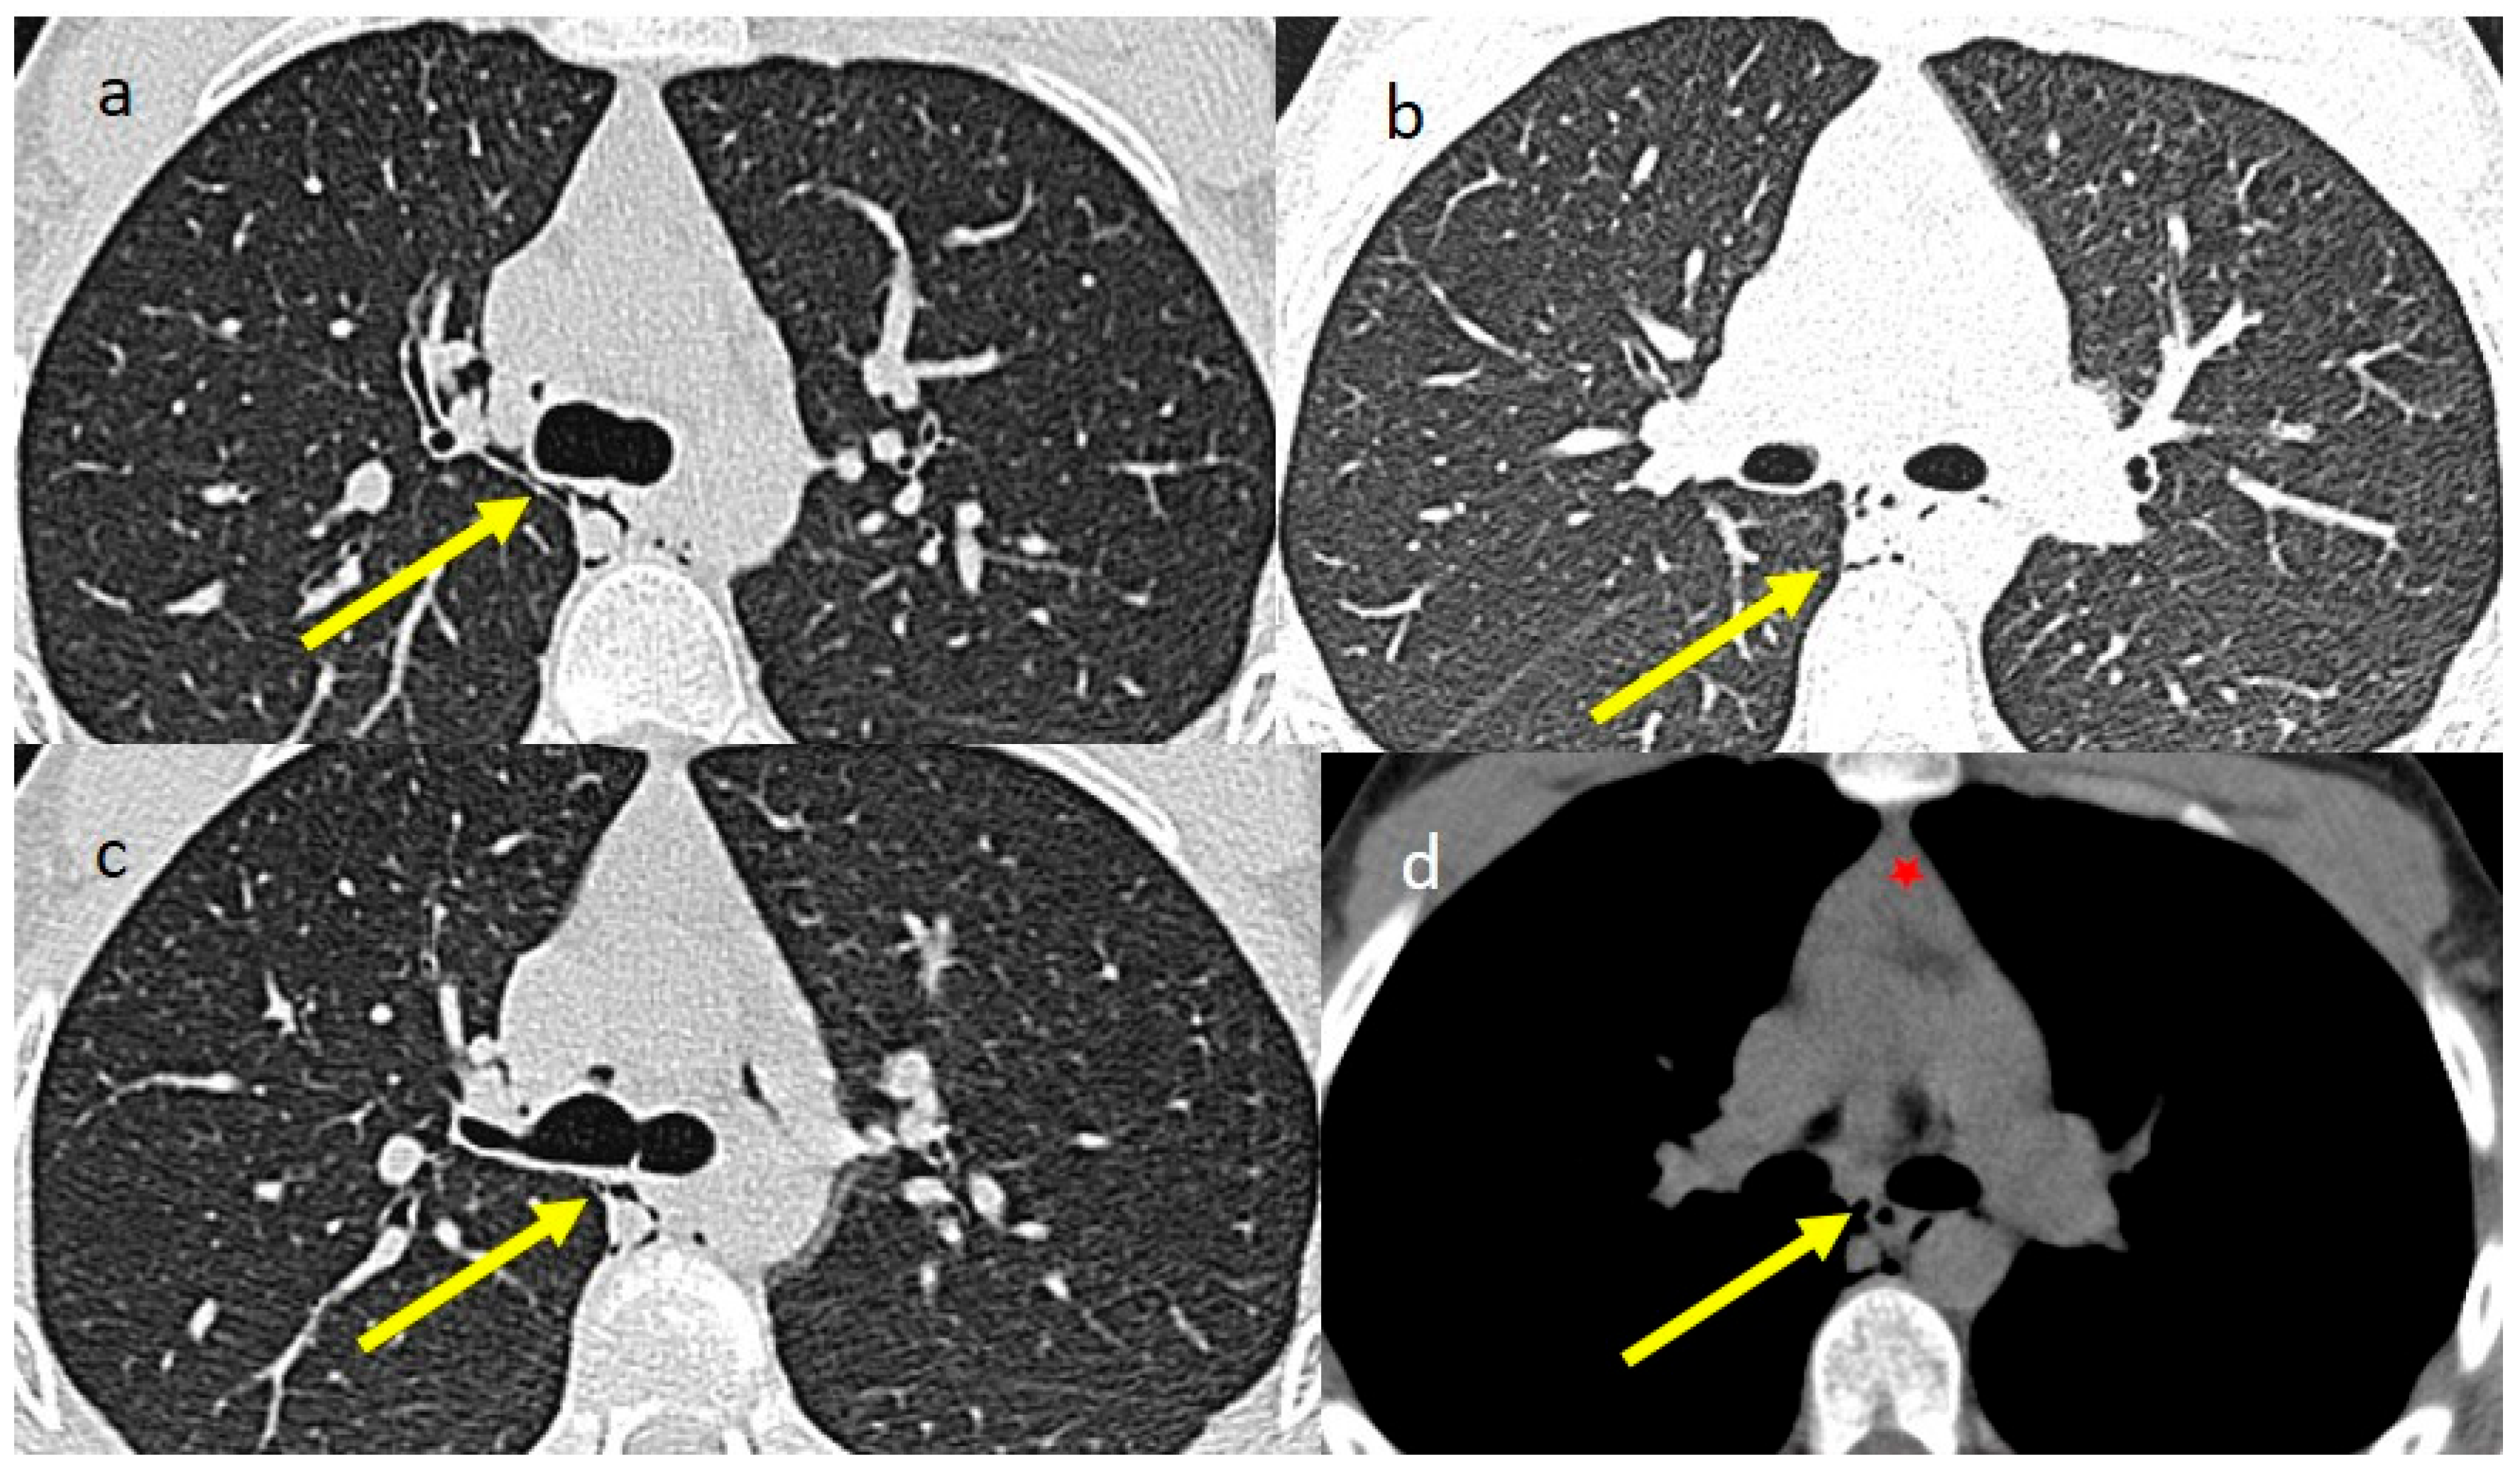

2. Case Presentations